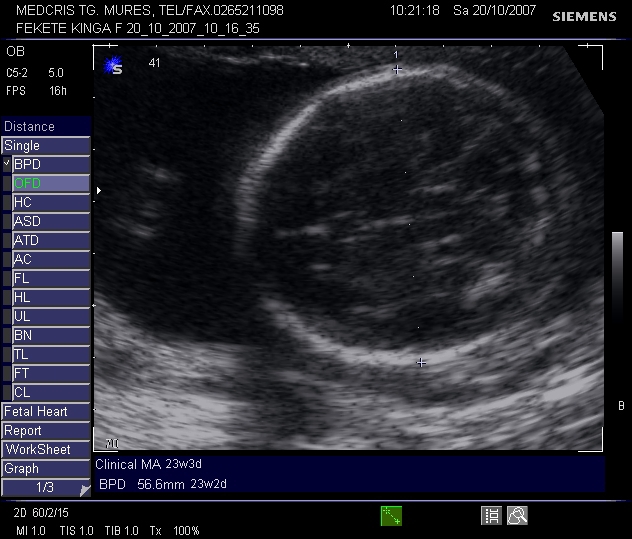

BIOMETRIA FETALA IN TRIMESTRELE II SI III DE SARCINA

Biometria fetala in trimestrele II si III de sarcina Indicatii: - urmarirea cresterii fetale normale sau discrepante inca din stadii timpurii (retardul de crestere intrauterina, maCiteste tot ... 932 cuvinte

Dimensiune mica

+ cu imagini |